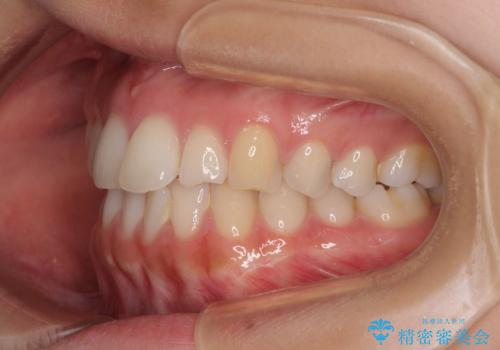

前歯の重なりをインビザライン・モデレートで矯正治療

- 上下前歯の重なりを気にして来院された患者様です。

安価なインビザラインパッケージを用いての治療を希望されており、デコボコの程度が中等度であったため、インビザライン・モデレートを用いて矯正治療を行うこととしました。